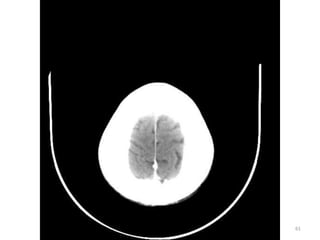

SUPRA TENTORIAL

82